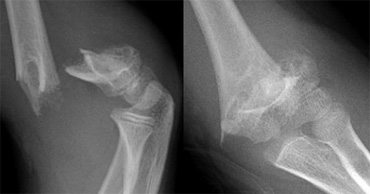

Gartland type III fracture Gartland type III fracture

Gartland type III fractures are completely dislocated and are at risk for malunion and neurovascular complications (figure).

They require reduction by closed or if necessary open means. Stabilisation is maintained with either two lateral pins or medial lateral cross pin technique.